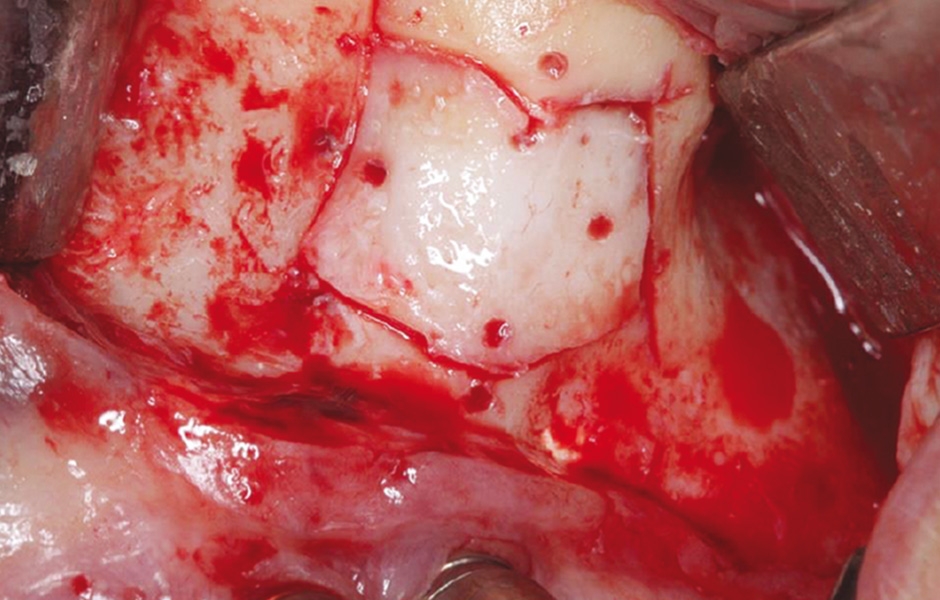

Do studie bylo zařazeno 10 pacientů s aspergilózou maxilárního sinu. U všech pacientů byl na panoramatických snímcích i na CBCT patrný radiopakní stín. CBCT navíc ukázalo, že čelistní dutina byla kompletně vyplněna homogenní patologickou masou. Chirurgická léčba sinu byla provedena za antibiotické profylaxe (Amoxicillin 2 g/den po dobu 7 dní) a intravenózní sedace (Midazolam). Kostní okénko bylo vytvořeno mikropilkou (DENTSPLY Implants), umožnilo bezpečný přístup do sinu. Po odklopení separovaného kostního fragmentu byla aspergilóza spolu s cizorodým materiálem kompletně odstraněna a dutina vypláchnuta peroxidem vodíku (H₂O₂ 3 %). Pro dodatečnou dezinfekci byla použita fotodynamická dekontaminace laserem HELBO (HELBO, Bredent Medical GmbH). Na závěr zákroku byla kostěná lamela vrácena zpět jako biologický uzávěr sinu a fixována resorbovatelnými stehy. Histopatologické vyšetření ve všech případech potvrdilo infekci aspergilózou. Po třech měsících, kdy CBCT potvrdilo nepřítomnost sinusové patologie a průchodné ostium, byla provedena augmentace kosti. Kostní bloky byly odebrány z retromolárové oblasti mandibuly a přeneseny ve 3D konfiguraci podle split-bone block techniky v kombinaci se sinus liftem. Sinus byl augmentován autologní kostí a biomateriálem (FRIOS Algipore®, DENTSPLY Implants) vrstvenou technikou. Po dalších třech měsících byly do augmentované oblasti zavedeny implantáty. O další tři měsíce později byly implantáty odhaleny a následně byla zhotovena definitivní protetická náhrada.“

Obr. 2: Vytvoření kostního okénka mikropilkou včetně perforací pro fixaci resorbovatelnými stehy.